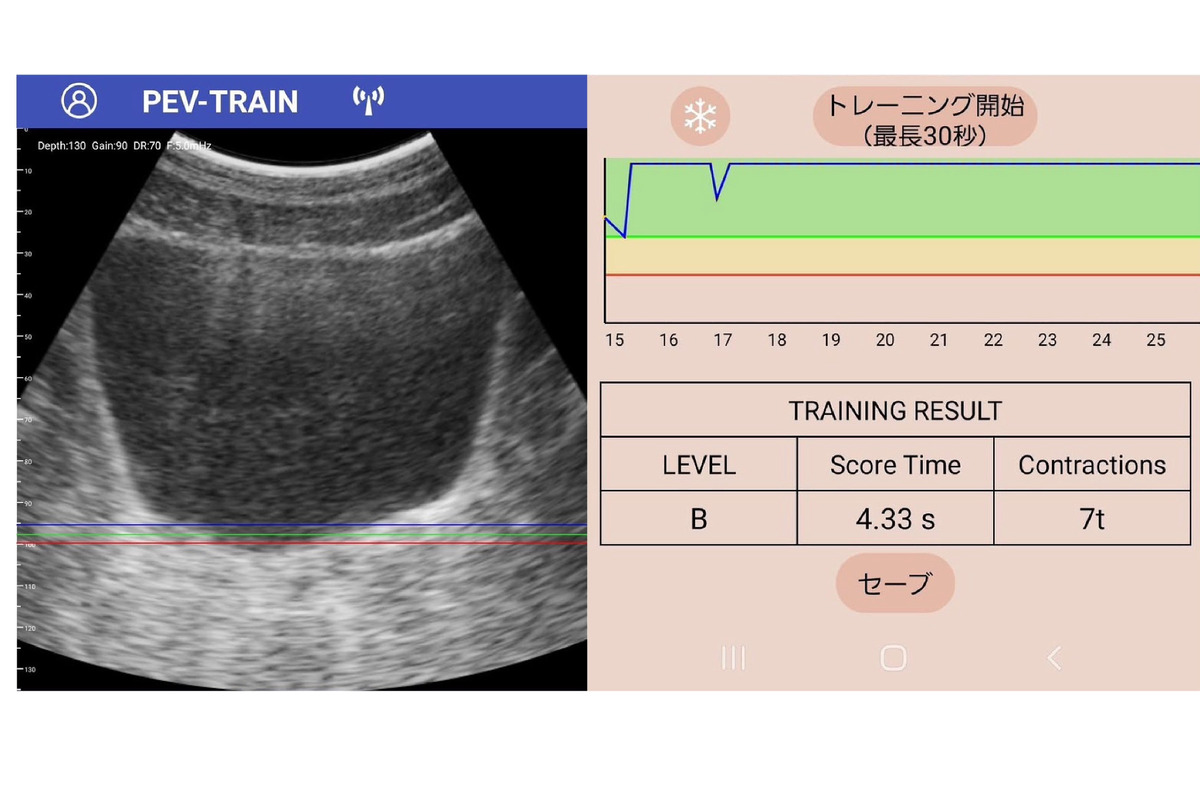

泌尿器科専門医と共同開発 スマホで「骨盤底トレーニング」できるアプリ 2枚目の写真・画像

泌尿器科専門医と共同開発 スマホで「骨盤底トレーニング」できるアプリ